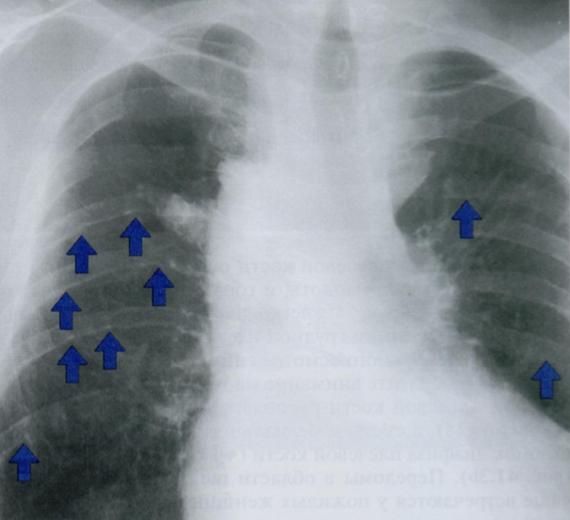

Данный снимок выполнен у одного и того же пожилого пациента с интервалом в 3 месяца. Обратите внимание на неравномерное утолщения ребер, отмеченные стрелками.

Дайте характеристику находке. Какие структуры грудной клетки наиболее часто поражаются?

Как отличить данную находку от костной мозоли после перелома?

Гематогенные метастазы - наиболее часто встречающиееся опухоли скелета грудной клетки у пожилых людей.

Особенно подозрительны кости, которые содержат костный мозг - ребра, грудина и позвоночник.

На повторном снимке мы видим прогрессию кортикального дефекта и увеличение размера метастаза.

На снимке слева ниже для сравнения показано веретенообразное утолщение после перелома ребра (костная мозоль), которое не сопровождается остеолическими изменениями кости. Важно визуально отличать костные мозоли и метастазы на ребрах.

На правом снимке также представлены участки остеолиза на телах грудных позвонков +/- снижение их высоты (отмечено стрелкой). При этом эти изменения не видны в ЗПП, поэтому показана БП.